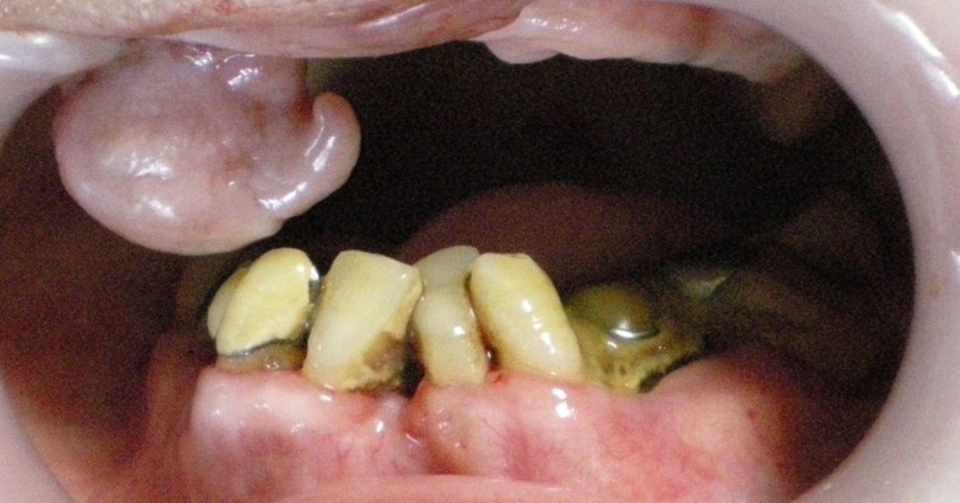

気付かないうちに進行しています 歯周病 たぼ歯科医院 経験豊富な専門医による診療

慢性歯周炎 電子コンテンツ 日本医事新報社

歯周病とは 症状と写真 口臭 歯周病 歯槽膿漏 について 大手町デンタルクリニック

歯周病ってなあに 公益社団法人神奈川県歯科医師会